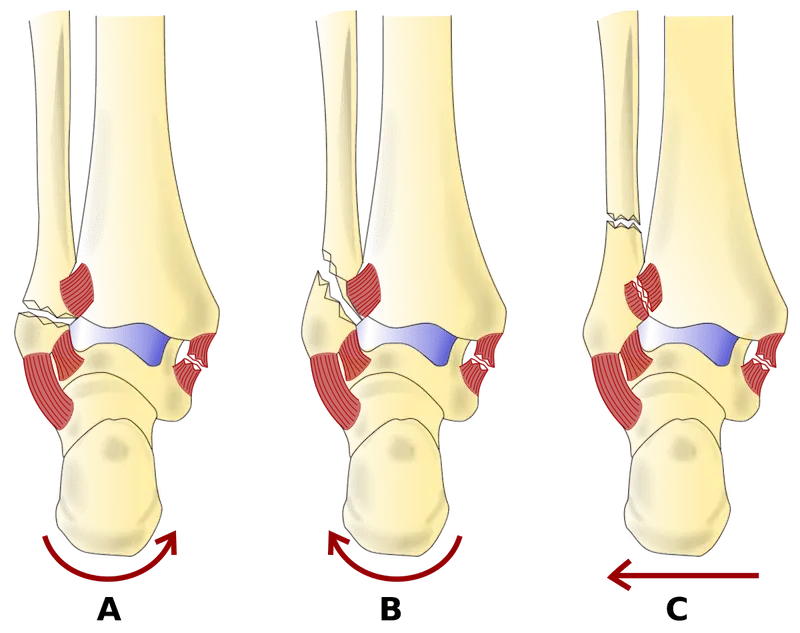

Type A Weber Ankle Fracture:

Type A fractures occur below the level of the ankle joint. These fractures involve the fibula and are typically stable, with minimal disruption to the ankle mortise (the joint formed by the tibia and talus). Treatment for type A fractures are usually conservative (physio and period of immobilisation).

Type B Weber Ankle Fracture:

Type B fractures occur at the level of the ankle joint itself. These fractures involve the fibula and may also involve the ligaments that stabilise the ankle joint. Type B fractures can be further subclassified as B1, B2, or B3, depending on the degree of ligamentous injury and joint instability.

Type C Weber Ankle Fracture:

Type C fractures occur above the level of the ankle joint. These fractures involve the fibula, but they also include a fracture of the tibia (the larger bone of the lower leg) or disruption of the syndesmosis, the ligamentous complex that connects the tibia and fibula. Type C fractures often require surgical intervention to restore the anatomical alignment of the bones and stabilize the joint.